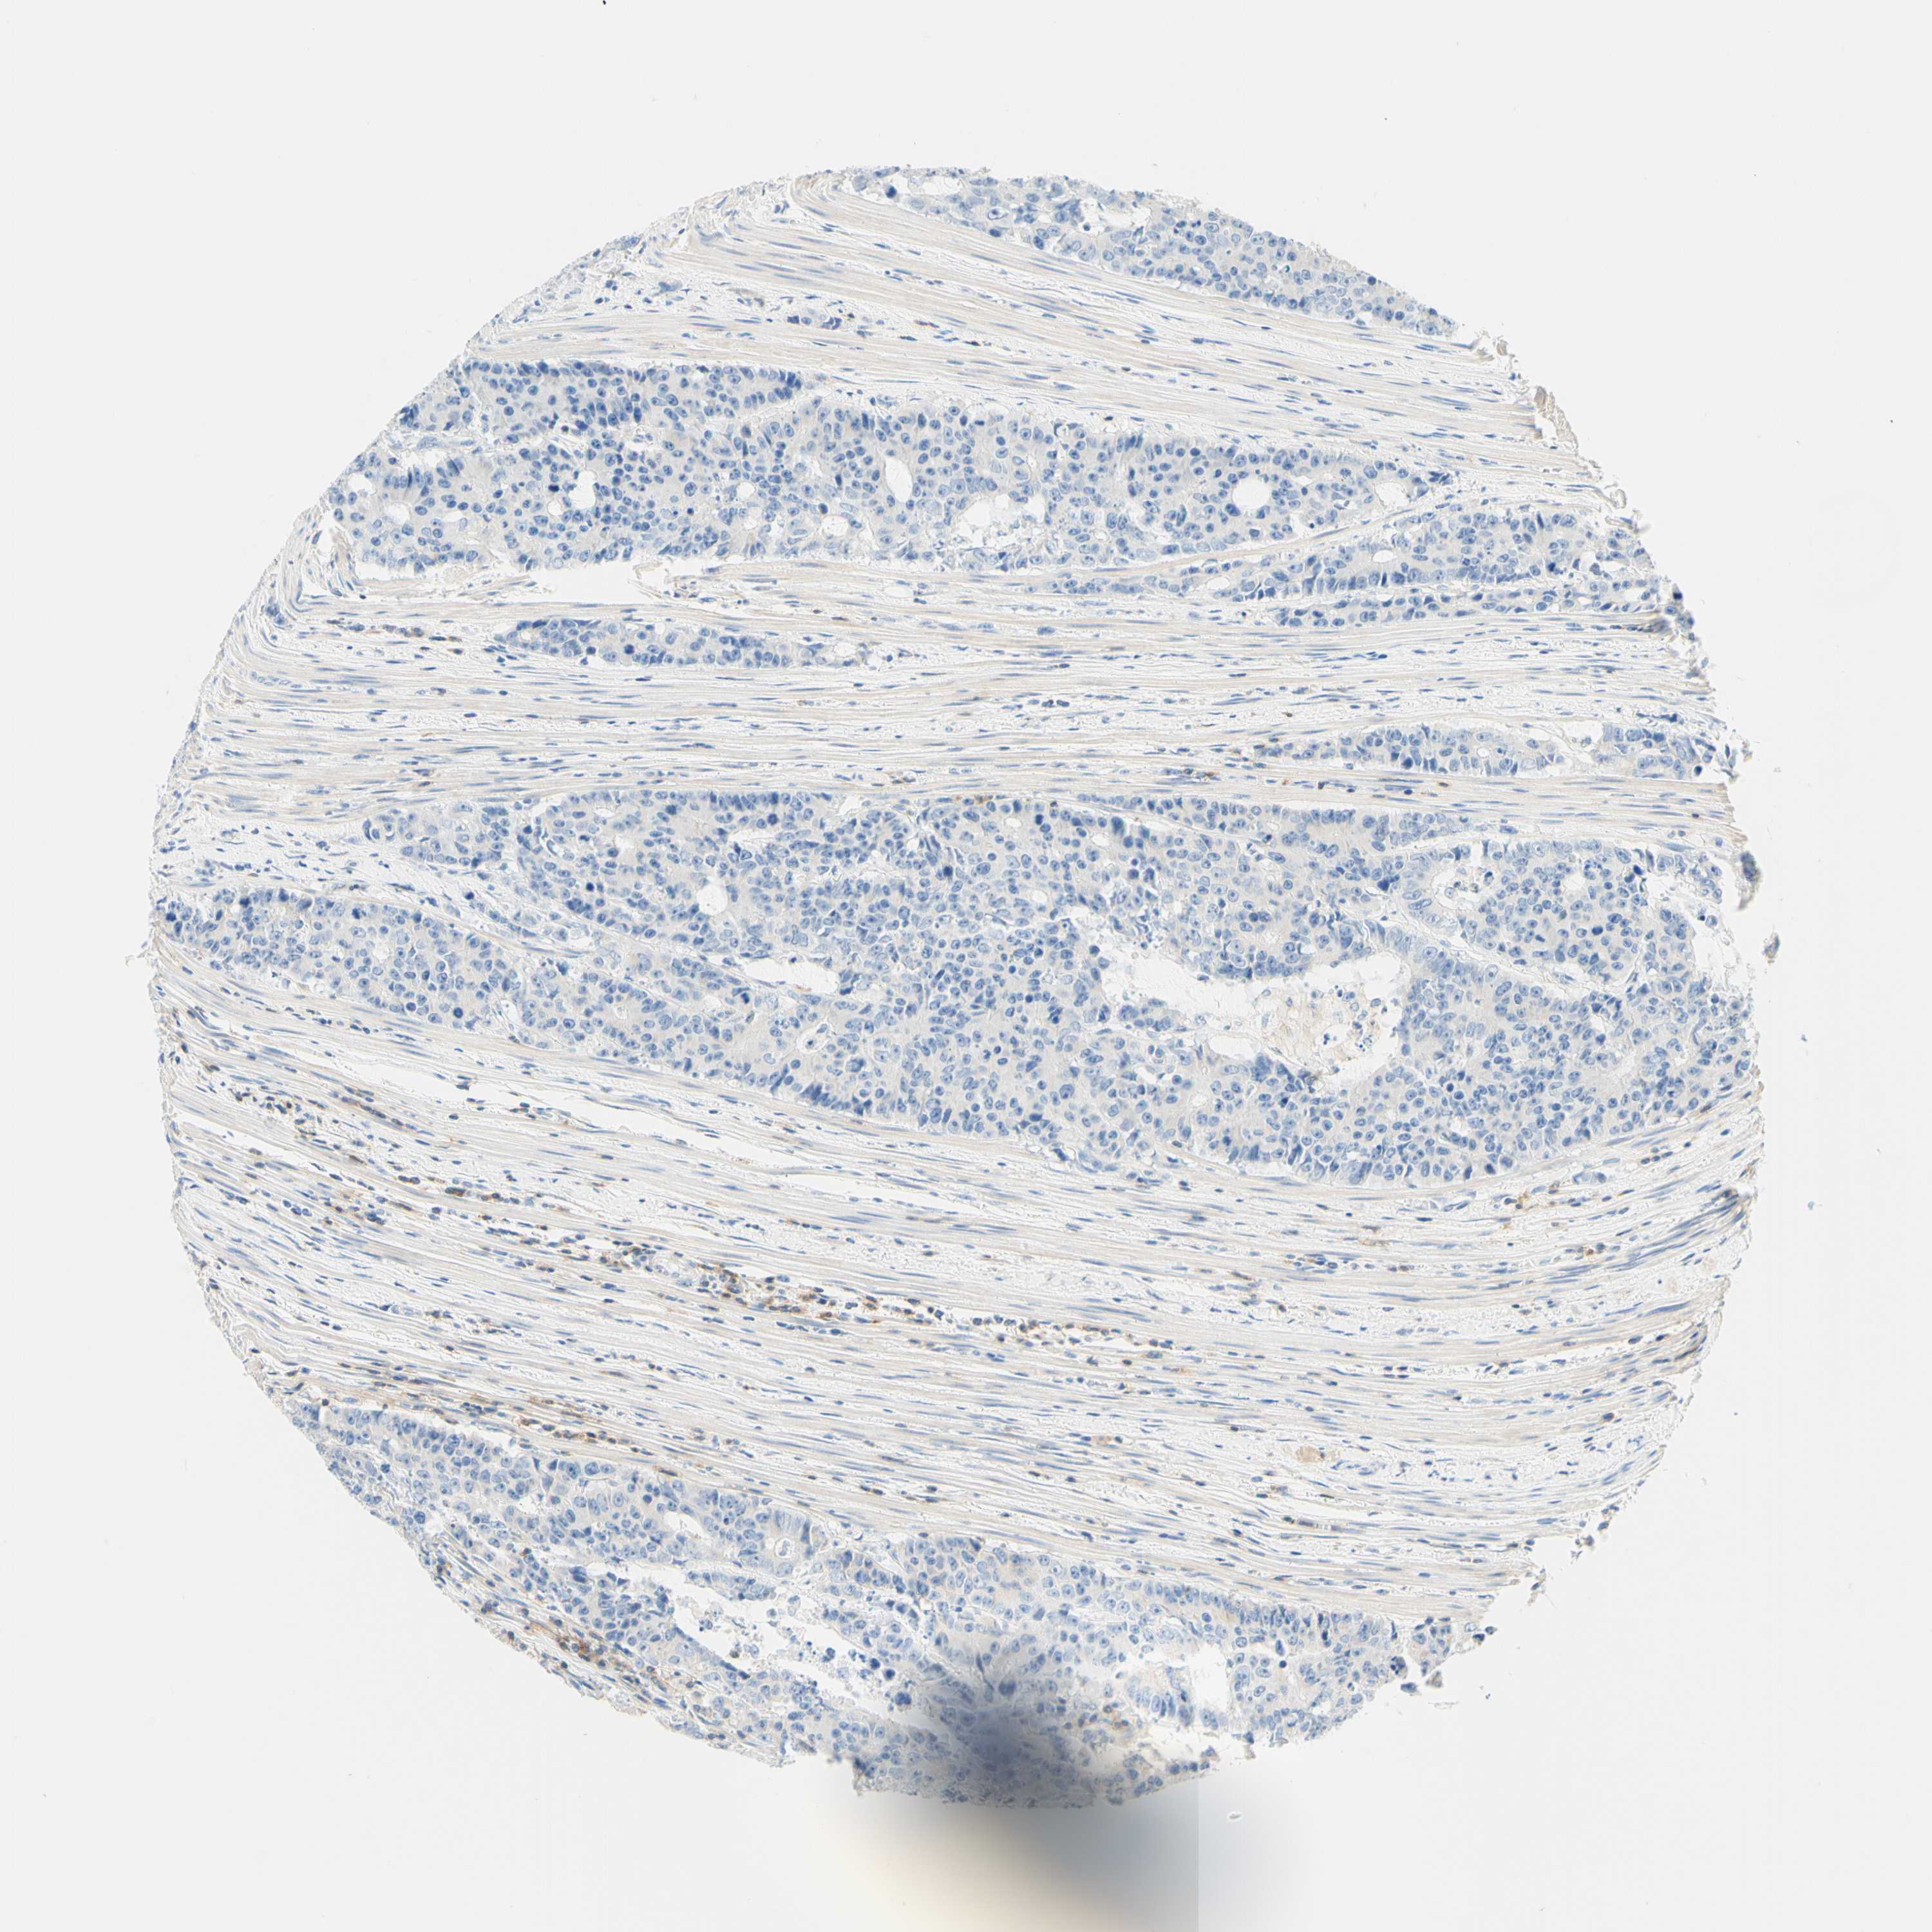

CANCER COLORECTAL CANCER Show tissue menu

COAD TCGA COAD VALIDATION READ TCGA READ VALIDATION PROTEIN COAD CPTAC PROTEIN EXPRESSION

Colorectal cancer

Human cancer

Colon adenocarcinoma